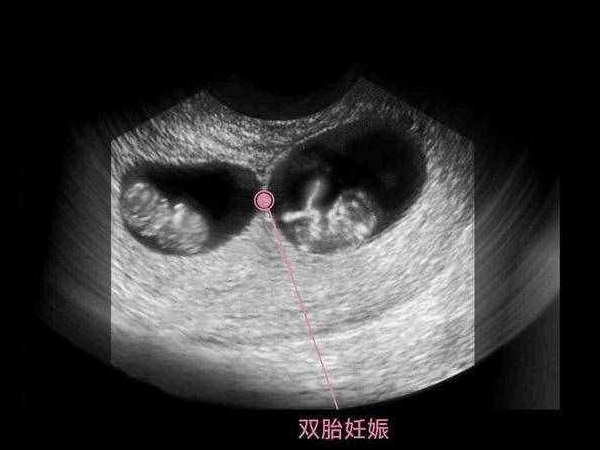

懷孕雙胞胎後女性體內的hcg就會不斷分泌,hcg值也會比單胎的正常值範圍更高,一般來說懷雙胞胎的正常hcg範圍為52.7-100.1nmol/L。由於人絨毛促性腺激素不斷上升主要是為了使胎兒在體內能夠更加穩定的生長髮育,所以如果女性在懷孕之後hcg翻倍良好的話,那麼就說明胚胎的發育也是比較良好的。反之,如果翻倍情況不好的話,可能也說明胚胎存在一定的異常。孕媽媽們需要及時瞭解hcg值的變化。一般來說,雙胞胎的母體更容易測出懷孕。雙胞胎的母體有更多的激素。懷孕8周左右就可以通過婦科B超發現宮腔內有兩個妊娠囊發育並且兩顆胎心同時跳動, 可以檢查雙胞胎懷孕,同時在抽血時血液中的絨毛膜促性腺激素水平,比單胎妊娠時的數值明顯增高。而關於懷雙胞胎會有哪些症狀,詳情在文中便可知曉。

在從整體上來說,雙胞胎會比單胎更早用試紙測出來懷孕,懷孕早期如何確認懷的是雙胞胎,如果出現以下特徵,那就說明懷雙胞胎的可能性很大。